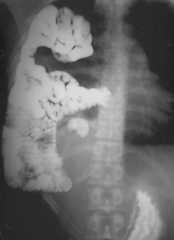

A thirty five year old male presented with breathlessness on routine exertion and symptoms of dyspepsia of a year duration. General physical examination was unremarkable, auscultation of the chest revealed presence of bowel sounds in the right side of the chest. Chest radiograph revealed a raised right hemidiaphragm, with its outlines not well discernible, mediastinal shift to the left and presence of air filled bowel loops in the right thoracic cavity (Fig 1). A provisional diagnosis of right sided diaphragmatic hernia was made and an upper gastrointestinal barium study was done which revealed presence of stomach, small intestine and parts of colon in the right thoracic cavity (Fig 2). A contrast enhanced CT scan of the thorax and abdomen was performed which confirmed presence of stomach, small intestine, large intestine and the right lobe of liver in the postero-lateral aspect of the thoracic cavity, discontinuity of the soft tissue line of the diaphragm with continuity of sub-diaphragmatic and supra-diaphragmatic densities through the defect suggestive of Bochdalek hernia (Fig 3). The right lobe of the liver was also hypoplastic. The patient was taken up for surgery and per operative findings revealed herniation of the stomach, coils of jejunum, ileum and colon through a smooth circular defect of 6cmx4cm size in the posterolateral aspect of the right hemidiphragm. The right lobe of the liver was hypoplastic and had herniated into the thoracic cavity. No hernial sac could be identified. The diaphragmatic defect was closed with polypropylene mesh and sutured in two layers with interrupted non-absorbable suture and the thoracic cavity was drained by a single chest tube. The patient had an uneventful postoperative recovery. A repeat upper GI barium study after 10 days of surgery revealed no evidence of any herniated bowel loop in the thoracic cavity (Fig 4).

Fig. 2.

Upper GI barium studies showing presence of stomach, small intestine and parts of colon in the right thoracic cavity